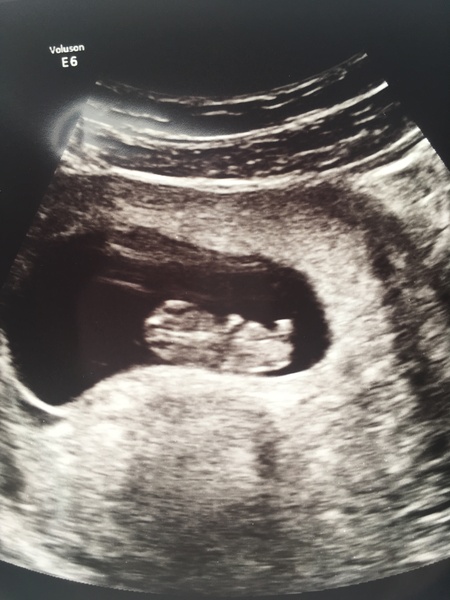

olicat · 02/09/2017 17:02

Great news heck ! Mine looks like a prawn

Babies due in April 2018

olicat · 02/09/2017 17:33

Wow suddenly looks very babylike! Have been avidly checking back for updates haha. Congrats 😁